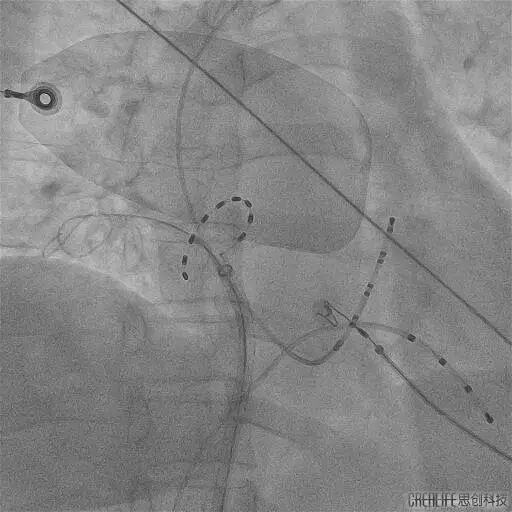

今年60岁的崔伯伯(化名)和59岁的张阿姨(化名)因房颤发作频繁,极大的影响日常生活,甚至呈焦虑状态,遂就诊武汉亚洲心脏病医院;在完善心脏彩超、食道超声及左房CT等一系列检查后,张劲林主任和韩宏伟主任经过充分的评估和与患者及家属的知情确认后,选择脉冲电场消融术为其治疗,该项技术以其高安全性、高效性和微创性,为房颤患者带来了更为优质的治疗选择。术中使用脉冲电场消融导管分别在四根肺静脉进行消融,每根肺静脉口内定位4个位置,前庭定位6-8个位置,逐次放电(电压1500V) 。每根肺静脉首次放电,肺静脉电位振幅即可明显下降至消失,四根肺静脉均完成肺静脉电隔离。

PS导管通过外鞘送入左心房,在二维引导下到达目标肺静脉,在导丝指引下调整导管成环进入肺静脉,使环形电极贴靠肺静脉口/前庭。

观察电极形变并明确电位,确认贴靠良好后依次对每个每支静脉进行口部4次+前庭6-8次的脉冲消融,对上腔静脉补充4次消融,完成四根肺静脉(PVI)和上腔静脉的环形隔离。

PS导管行RIPV消融